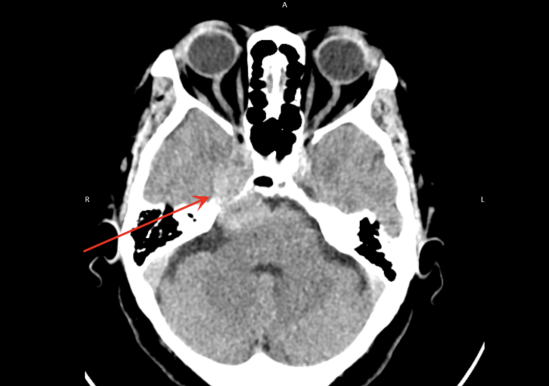

半个月前,一场突如其来的不适打破了李阿婆平静的生活 —— 莫名头晕症状,行走时摇摇晃晃,右耳听力也随之下降。当地医院颅脑 MRI 检查提示右侧岩尖区存在占位,疑似三叉神经鞘膜瘤。为寻求精准的治疗,家属带着李阿婆辗转咨询多家国内顶尖医院,得到的结论,如出一辙且令人绝望:「肿瘤位置太糟了,压着颈内动脉、小脑、脑干,还挨着好几条重要神经,手术风险极高,术后可能留后遗症,甚至有生命危险。」 接连的负面消息,让满怀期待的一家人陷入绝境。